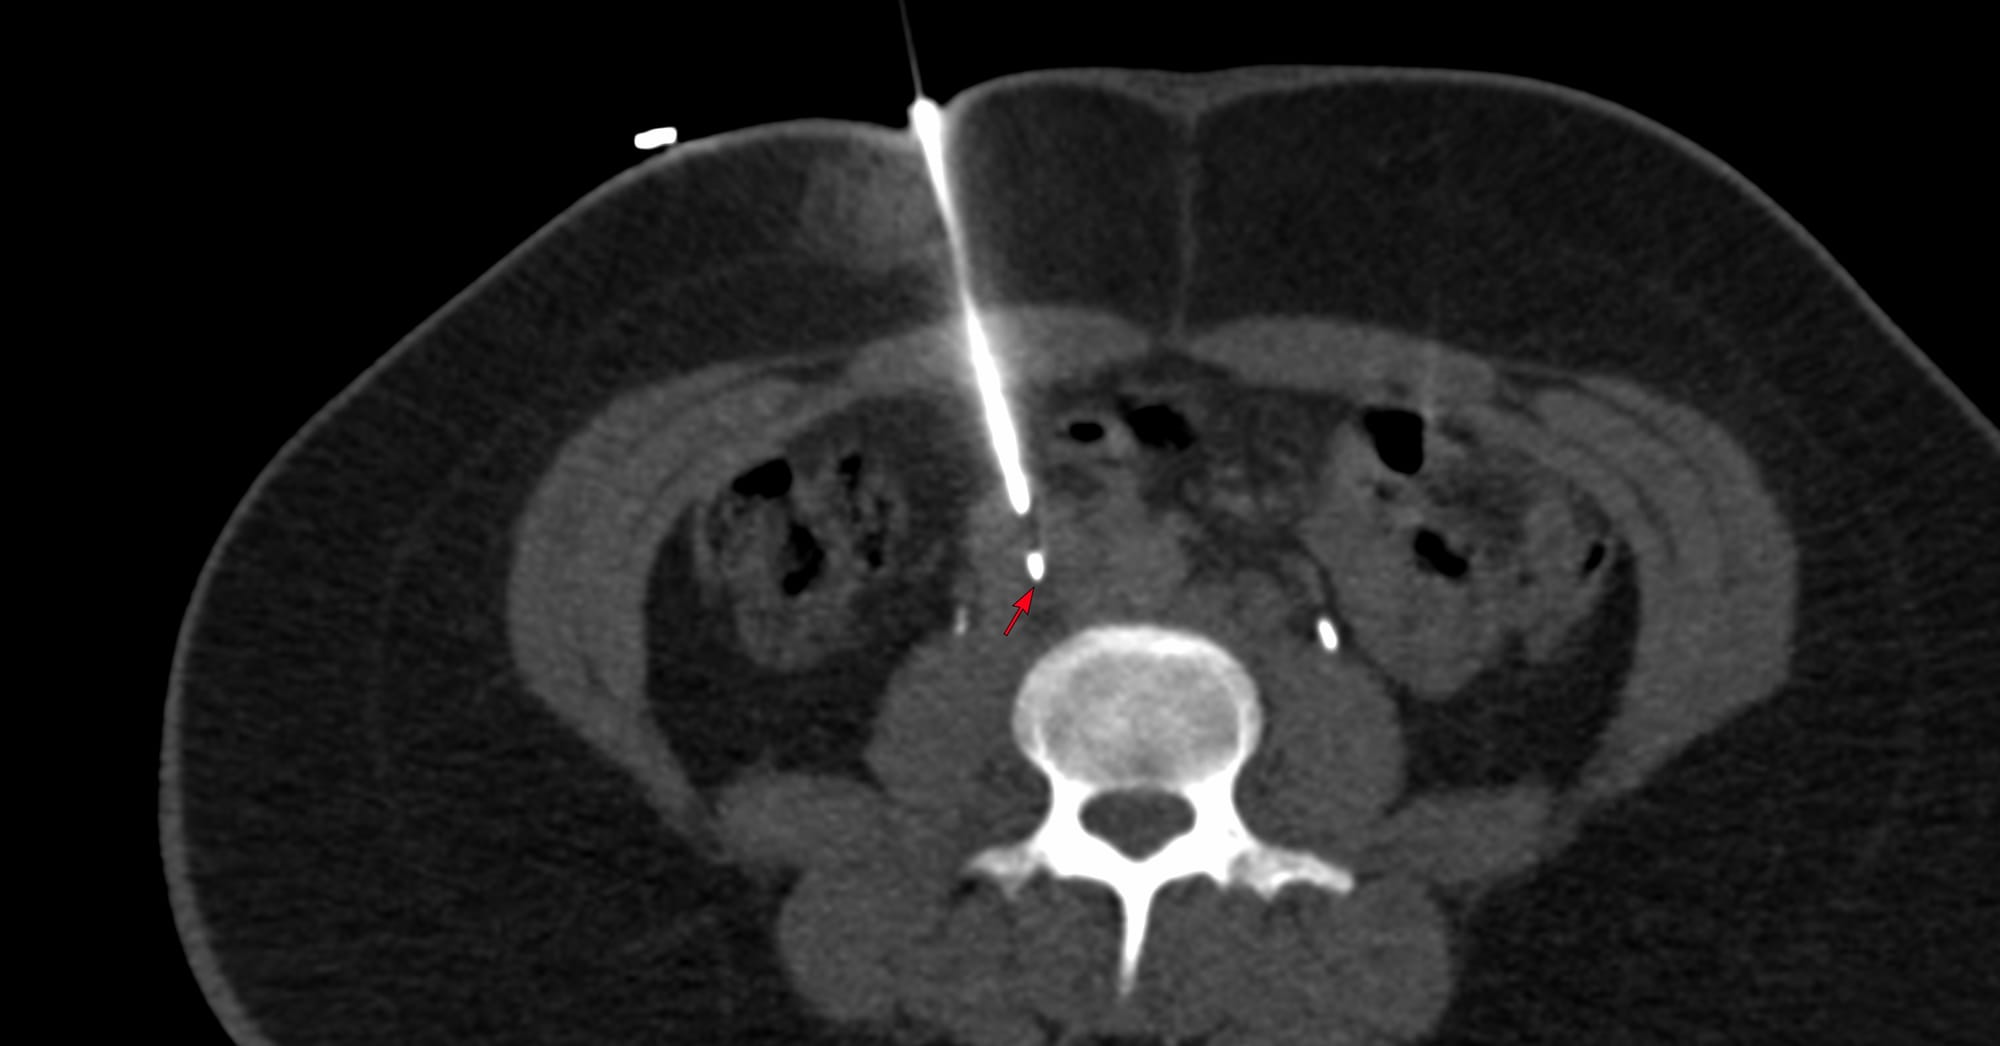

Case 172 - Right Adrenal Gland Biopsy Using an Ipsilateral Up Approach with Hydrodissection

Bhavin Jankharia - 31 December 2025